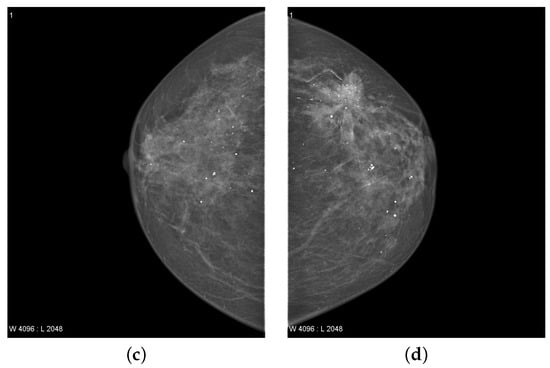

In the breast, cancer cells can increase to the lymph nodes and affect other body parts, i.e., lungs. Breast cancer usually begins with ductal dysfunction (invasive ductal carcinoma). Although, it can also originate in glandular tissues and other cells called lobules and breast tissue [15]. The researchers also found that changes in hormones, lifestyle, and the environment also increase the risk of breast cancer [16,17]. Low dose X-ray examination of the breast is utilized to envisage the internal structure of the breast. This process is medically called mammography. This is evaluated as the best suitable approach for the detection of breast cancer. Compared to previously used equipment, mammography shows the breast to a much lower radiation dose [18]. It is one of the most reliable screening tools and has been shown to be a significant approach for early breast cancer detection in recent times [19]. A mammogram of each breast was recorded in two different views, namely the medial-lateral oblique (MLO) view and the cranio-caudal (CC) view as shown in Figure 1. Estimated new cases recorded in 2021 were 281,550 and the percentage of all the new cancer cases was 14.8% in the U.S. The estimated deaths in 2021 was around 43,600 having a percentage of 7.2%. The 5-year relative survival rate of breast cancer from 2014 to 2019 was 92.16% in the U.S [20].

Figure 1.

The breast mammogram of a patient [21]. (a,b) Right and left medial-lateral oblique (MLO) view, (c,d) Right and left cranio-caudal (CC) view.